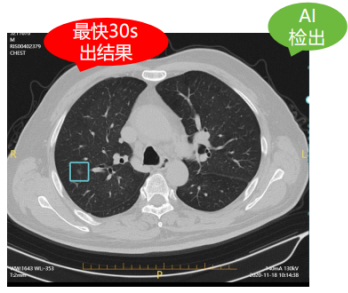

以肺結(jié)節(jié)人工智能篩查為例,正常的一個(gè)肺部CT平掃檢查具有幾百?gòu)埰瑢?,而一位熟練的診斷醫(yī)生想要從這些復(fù)雜的影像中發(fā)現(xiàn)并診斷病灶可能需要花上20-30分鐘,甚至是更長(zhǎng)時(shí)間。而通過(guò)AI智能影像輔助診斷技術(shù)的精準(zhǔn)定位與檢測(cè),自動(dòng)檢出實(shí)性、磨玻璃、鈣化以及混合結(jié)節(jié)、疑似腫塊等,僅需30秒便可自動(dòng)生成結(jié)構(gòu)化影像報(bào)告供醫(yī)生審查,雙肺結(jié)節(jié)檢出率高達(dá)99.64%!對(duì)0.5mm的微小結(jié)節(jié)都能瞬間定位,快速標(biāo)記結(jié)節(jié)大小、密度,并初步分辨良惡性,有效幫助醫(yī)生更加精準(zhǔn)篩查肺結(jié)節(jié),使肺癌患者及早得到良好診治。